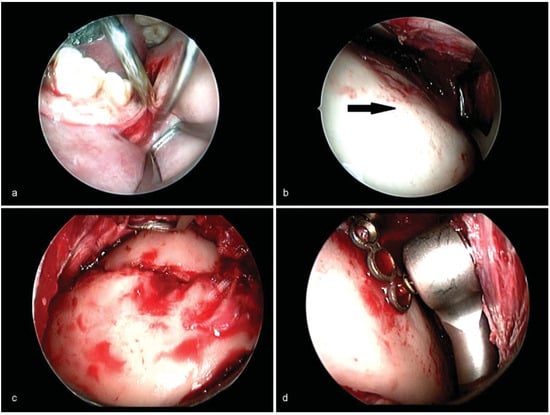

Figure 3.

(a) “S”-shaped curvilinear incision along the anterior border of ramus for transoral approach. (b) Optical cavity created in the subperiosteal plane over lateral surface of ramus. Arrow shows the lateral surface of the ramus. (c) Endoscopic visualization of reduced laterally displaced fracture. (d) Endoscopic visualization of placement of screws using right angled driver.